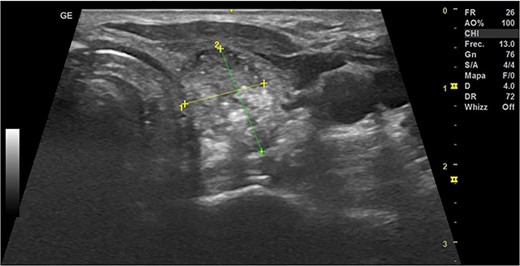

In May 2022, a thyroid ultrasound revealed a solid isoechoic left lobe TN measuring 12 × 11 × 13 mm, characterized by microcalcifications and irregular borders (Fig. 1). The color-flow Doppler ultrasound indicated increased perfusion, leading to its classification as a TI-RADS 5 nodule (Fig. 2). Elastography yielded a value of 2.2 (Fig. 3). Fine-needle aspiration confirmed Bethesda VI, consistent with thyroid papillary carcinoma.

Thyroid ultrasound: transversal view, left lobe nodule identification and measures. Pre-RFA procedure.